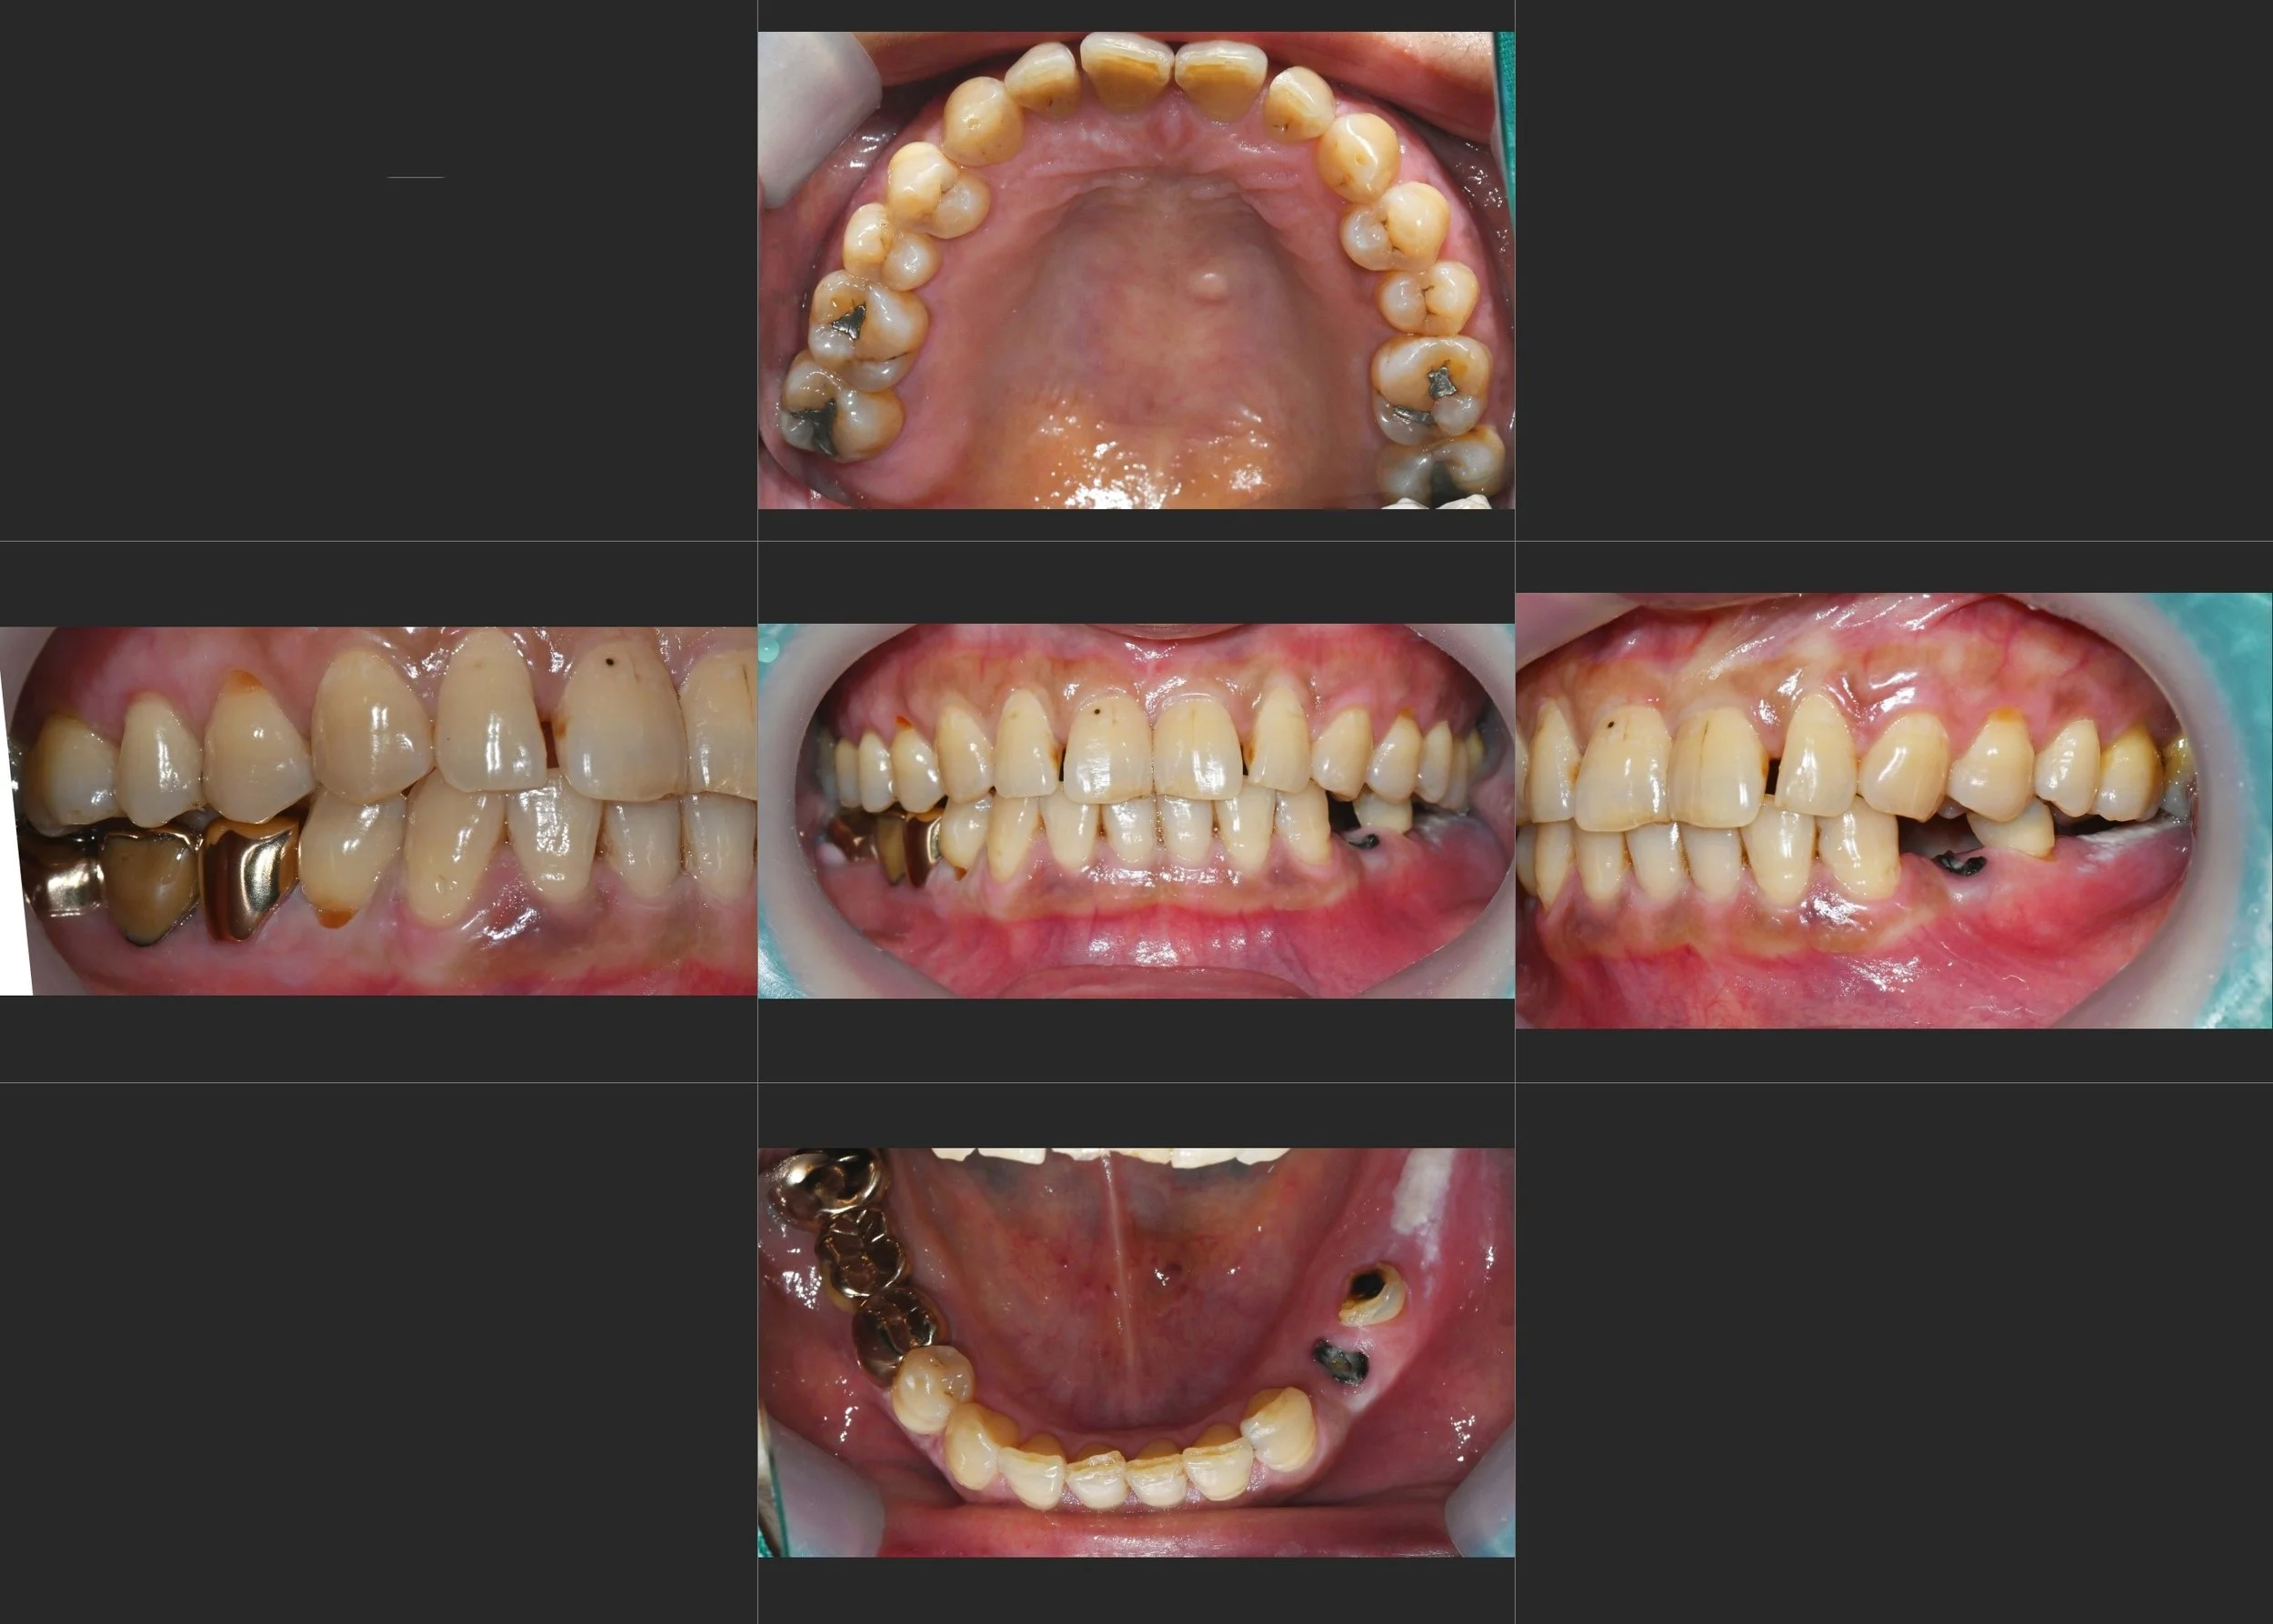

INTRA ORAL - AFTER